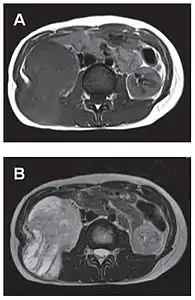

L'imagerie par résonance magnétique permet une exploration complémentaire dans certaines localisations. Elle est surtout réalisée pour les tumeurs du système nerveux central[8],[12],[43], du foie et du pelvis[31],[41]. Elle évalue mieux les différences de densité intra-tumorale et permet d'affirmer l'absence d'envahissement des tissus mous et des structures osseuses voisines[20]. Les tumeurs fibreuses solitaires ont un aspect d'isosignal en séquence T1 et d'hypersignal en T2, et se rehaussent après l'injection de gadolinium[31]. Cependant, dans le système nerveux central, elles ne présentent pas de critères caractéristiques permettant de poser un diagnostic de manière uniquement radiologique[12] et, en pré-opératoire, sont souvent confondues avec un méningiome[43].

- Tumeur fibreuse solitaire du rétropéritoine

Aspect IRM, en séquence T1 (A) et T2 (B)[44].